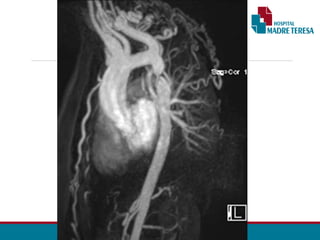

ANGIO TOMOGRAFIA

• Segmento estenosado

• Circulação colateral

• Planejamento cirúrgico

•Acompanhamento pós - OP

ANGIOTOMOGRAFIA DA AORTA TOTAL – 28/05:

• Presença de volumosa dilatação aneurismática do segmento tubular

ascendente aórtico, com o diâmetro de até 74 mm, sem trombo.

• Nota-se a redução moderada do diâmetro luminal aórtico do arco, sendo

mais intenso na região do istmo (diâmetro mínimo luminal efetivo no istmo é

de aproximadamente 6,5 mm), havendo dilatação fusiforme pós-

estenótica no terço proximal descendente aórtico com até 36 mm.

• O segmento mais distal descendente da aorta apresenta o diâmetro normal.

• São evidenciadas diversas artérias dilatadas moderadamente

intercostais da metade superior, bilaterais, notando-se ainda leve /

moderada dilatação bilateral das artérias torácicas internas.

•Artérias ilíacas comuns, internas e externas estão patentes.